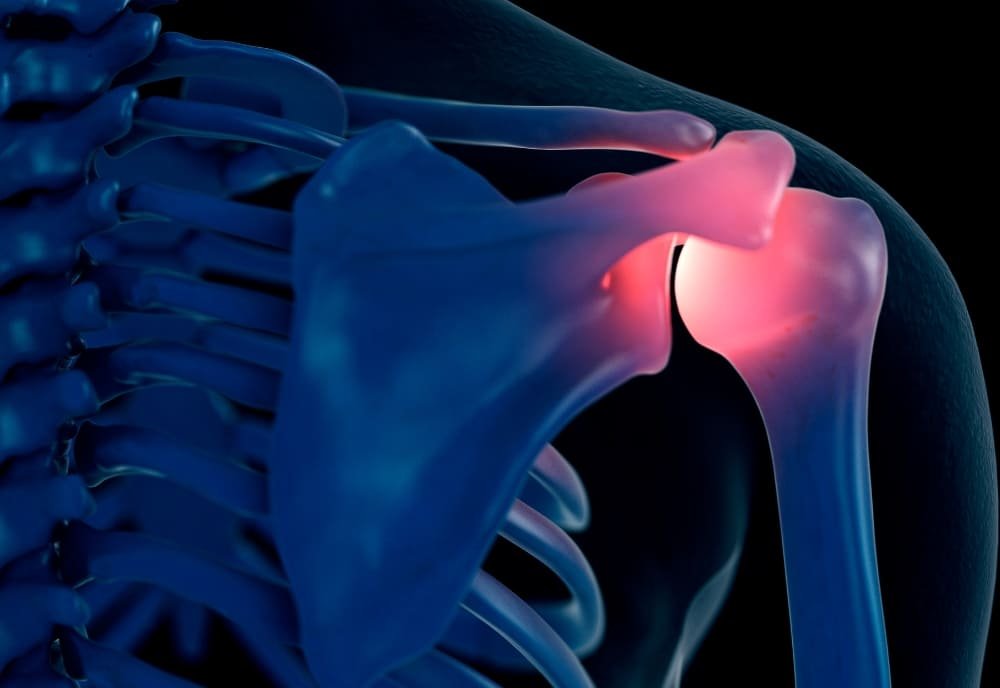

A artrose é uma doença degenerativa crônica das articulações, caracterizada pelo desgaste progressivo da cartilagem que reveste as superfícies articulares, causando inflamação, dor e limitações de movimento. Embora possa afetar qualquer articulação, as mais comuns são os joelhos, quadris, coluna vertebral e mãos, comprometendo a mobilidade e qualidade de vida do paciente. Este desgaste natural da cartilagem é um processo que geralmente ocorre com o envelhecimento, mas também pode ser acelerado por fatores como lesões articulares anteriores, sobrepeso, atividades de alto impacto ou predisposição genética.

Os principais sintomas da artrose incluem dor crônica, rigidez nas articulações, dificuldade para realizar movimentos simples como caminhar, subir escadas ou até segurar objetos. Em estágios mais avançados, a dor pode ser constante e dificultar a realização de atividades cotidianas, impactando significativamente a qualidade de vida do paciente.